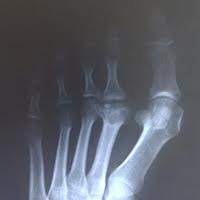

ДИАГНОСТИКА

Диагноз устанавливается на основании жалоб больного, клинической картины заболевания, рентгенологического исследования. Дополнительно проводят КТ и ангиографию.

Медицинские процедуры, проводимые при заболевании болезнь келлера: Рентген, Компьютерная томография, Ангиография